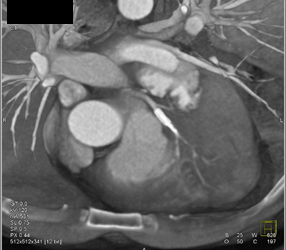

Diagnosis

Patent LAD Stent